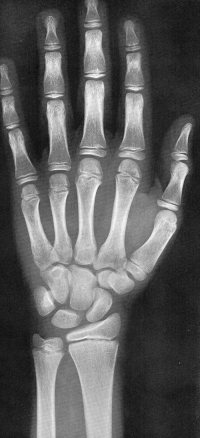

Sexo Masculino

Recém-Nascido

idade óssea - RN